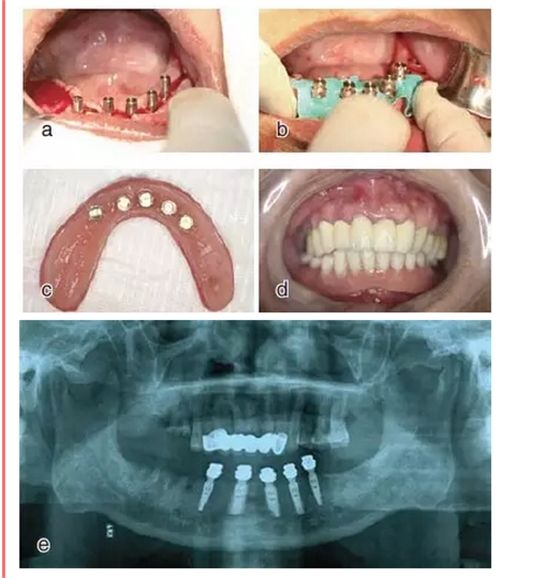

設(shè)計切口,剝離黏骨膜后,將截骨導(dǎo)板戴到骨面上,用咬骨鉗沿著截骨導(dǎo)板平面進(jìn)行截骨,并用骨銼修整骨平面,截骨完成后將種植導(dǎo)板固定在骨面上進(jìn)行種植備孔,完成后植入種植體。注意截骨平面要平整,否則影響種植導(dǎo)板的就位。

戴上套筒冠基臺進(jìn)行即刻修復(fù)。注意不是所有植入的種植體都可以進(jìn)行即刻修復(fù),醫(yī)師可以通過扭力值并結(jié)合ISQ松動度測量值來選擇修復(fù)的種植體。

圖18

進(jìn)行即刻修復(fù):a.戴上基臺;b.在基臺上戴入套筒冠;c. 套筒冠固位到原有義齒上;d.患者戴上有套筒冠的覆蓋義齒;e.

即刻修復(fù)完成后曲面體層片